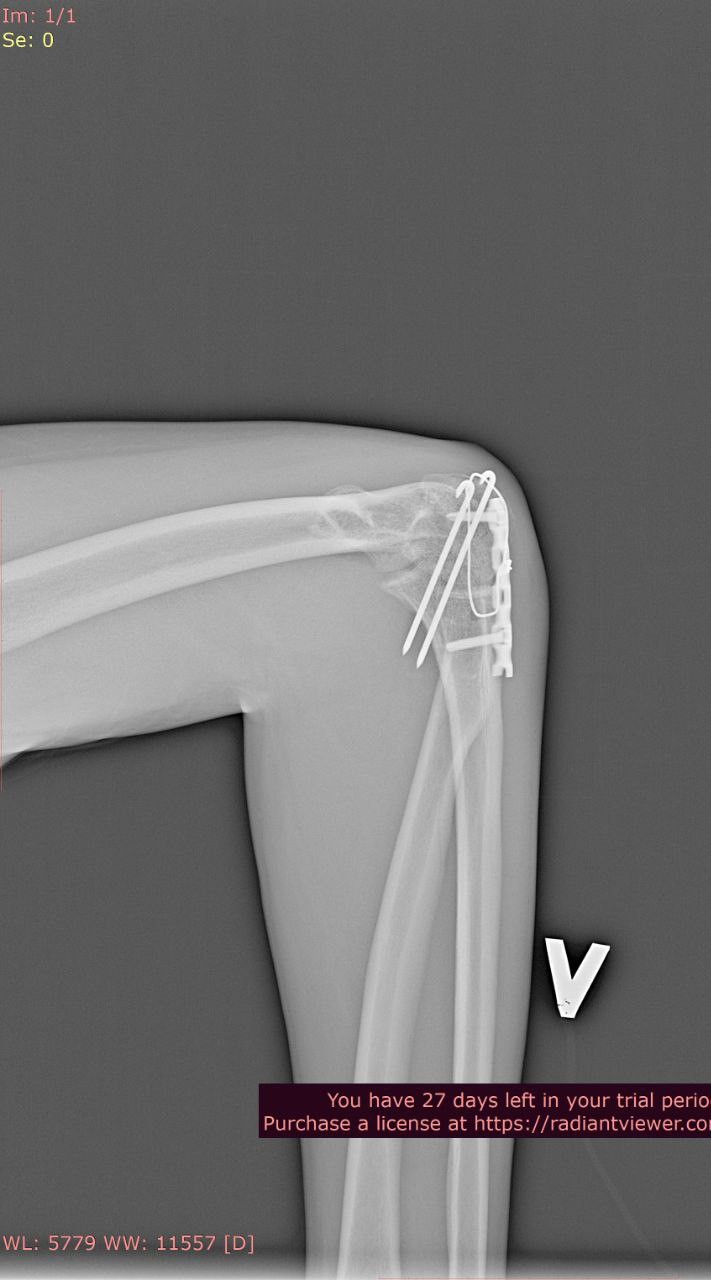

Добрый день. Два года назад упал с большой высоты, из-за чего мне установили металлоконструкции в плечевой и локтевой костях левой руки и в лучевой кости правой руки. Снимки ниже. Также имеются ограничения кисти на правой руке (из-за наличия пластины в лучевой кости), она разгибается максимум на 60 градусов из 90. Также, локтевая кость не разгибается до конца на пять градусов (что несущественно, но факт есть). Хотел бы уточнить, имею ли я возможность в моей ситуации получить категорию "В"? Спасибо.

Локтевая кость

Л2.jpg